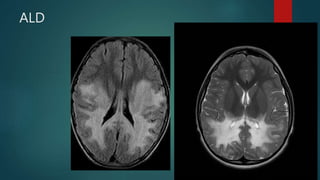

ALD

• #50 five different MRI patterns of adrenoleukodystrophy based on the involved anatomic locations and MR patterns of progression: deep white matter in the parieto-occipital lobes and splenium of the corpus callosum (66% of cases, chiefly in children); may include lesions of the visual and auditory pathways frontal lobe or genu of the corpus callosum (15.5%, mostly in adolescents) frontopontine or corticospinal projection fibres (12%, mostly in adults) cerebellar white matter (1%, mostly in adolescents) combined parieto-occipital and frontal white matter (2.5%, mostly children) There tends to be cortical and subcortical U-fibre sparing